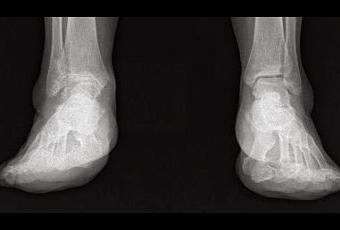

Primero es mayor de 60 años y, por lo tanto se cumple la expectativa de no tener, posiblemente, que recambiar la prótesis cuando ésta se deteriore.Segundo la demanda funcional normal del paciente es pequeña, es decir, no hace mucho deporte ni tiene un trabajo muy pesado.Y tercero, la calidad del hueso es aceptable y no presenta grandes deformidades.En caso de no cumplirse éstos supuestos hay, lógicamente, otras posibilidades de tratamiento, más adecuadas en cada caso.La principal ventaja de ésta cirugía es que permite recambiar una articulación dolorosa con poca movilidad normalmente, por una nueva con mejor movilidad y sin dolor, en contraposición con la cirugía convencional como por ejemplo, una artrodesis o fusión de la articulación (deja de doler pero se pierde la movilidad).Los inconvenientes principales son el precio que es alto, y la dificultad técnica de la intervención quirurgica.Abajo os muestro las radiografías de antes y después de la operación: